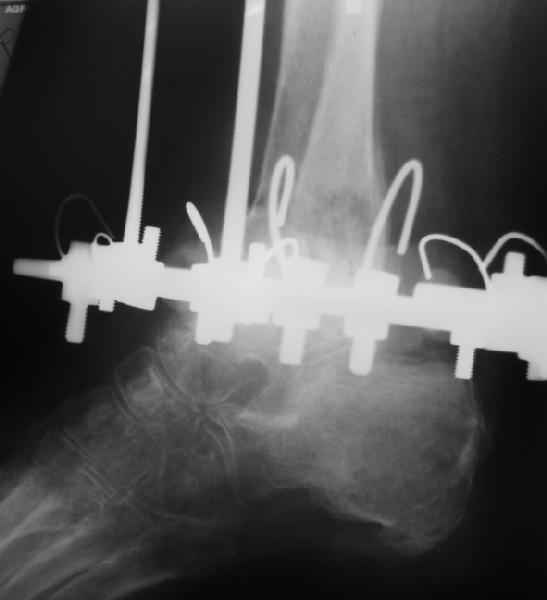

Пациентка 56лет поступила через 5,5 мес. после открытого 2-х лодыжечного перелома,

наружного вывиха правой стопы, осложнённого гнойным артритом.

через 3 недели после травмы в ОКБ выполнена артротомия, некрсеквестрэктомия б/берцовой

кости, ещё через неделю - аутодермопластика по Тиршу. К нам больная поступила через 5,5 мес.

Выполнен ЧКО, остеотомия м/берцовой кости, аппаратное вправление вывиха. Планируется

артродез голеностопного сустава. По медиальной поверхности голени на месте

аутодермопластики сформировался грубый рубец, спаянный с б/берцовой костью. Больная

ходит на костылях с частичной опорой на правую стопу. ВОПРОС: 1) возможно ли в данной ситуации

обойтись компрессионным артродезом в АВФ? 2) какой вид кожной пластики и в какие сроки

целесообразен?